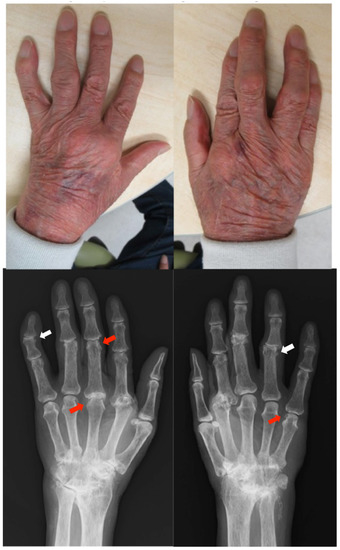

2.6. Case 6

Patient: Man in his 40s

2.7. Case 7

Patient: Man in his 50s